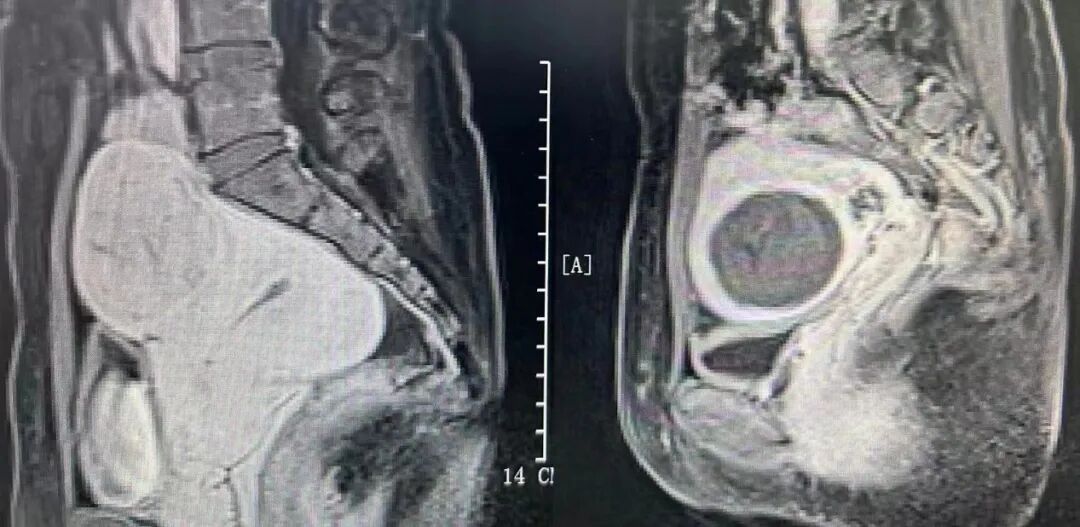

手術(shù)在鎮(zhèn)靜鎮(zhèn)痛下進(jìn)行,分別歷時35分鐘、68分鐘順利完成兩臺手術(shù)。與傳統(tǒng)的開腹手術(shù)、腔鏡手術(shù)相比,聚焦超聲消融手術(shù)具有無創(chuàng)傷、并發(fā)癥少、預(yù)后快等優(yōu)點,對身體子宮傷害小,術(shù)后恢復(fù)快。兩位子宮肌瘤患者對治療非常滿意,對醫(yī)生的精湛醫(yī)術(shù)表示衷心感謝,術(shù)后第二天均順利出院。

本技術(shù)已用于子宮肌瘤、子宮腺肌病、胎盤植入、瘢痕妊娠、腹壁子宮內(nèi)膜異位癥、宮頸炎、宮頸HPV感染、外陰白斑等多種疾病的治療,截至目前已成功治療接近2000例患者,取得了滿意的治療效果。